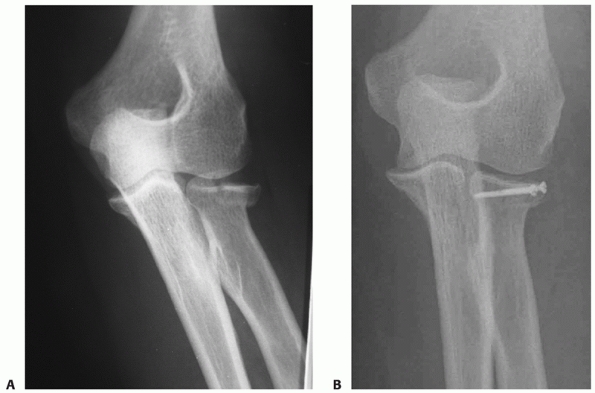

FIGURE 32-17 The so-called terrible triad of the elbow consists of dislocation of the elbow with fractures of the coronoid and radial head. A.

The coronoid fragment is the triangular fragment anterior to the trochlea. After manipulative reduction, this elbow could not be kept reduced despite cast immobilization. B. The coronoid fracture is a transverse fracture of the tip as seen on this three-dimensional computed tomography reconstruction. C. Operative fixation of the coronoid, replacement of the radial head, and reattachment of the lateral collateral ligament complex to the lateral epicondyle restored good elbow function. |